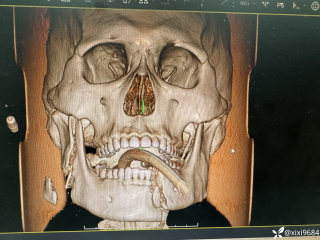

灼见|如果是你,如何处置山东男孩(多器官切除病例)

西地兰vip普外科医师

文/西地兰 特别声明:所有观点仅代表个人言论 特别声明:与当事双方均无利益相关 山东男孩,目前全网沸沸扬扬,看过一些观点,直言不讳地说,大多偏颇。要么一股脑地指责医方的全责,甚至有说千万别在县医院看病。要么又为医方无休止的遮羞,认为这样的手术在县医院做下来已经非常了不起。而我想到的是,以后面临类似的病例,我们怎么办?那么我们不如来一次专业的病案讨论。既然是事后讨论,难免有事后诸葛亮的感觉,但是假如下一次,同行们遭遇这样的病例,如何处置?这是医疗行业所面临的问题。希望我整理的这些思路和相关病例,对同行们有所帮助!就目前的资讯外界不足以判断是否需要急诊,如果需要急诊,那么只能根据术中所见进行处理,

玩耍被撞后10岁男孩被诊断有肿瘤,多器官切除 当地卫健局:医院存在问题,已立案

丁香医小白普外科医师

2023年10月26日,来自山东菏泽市成武县的小烨和他家人的命运被彻底改变了。这个原本阳光、可爱的小男孩在一次意外被撞击后,在医院检查出了腹腔内存在肿瘤,并在手术中被切除了包括十二指肠、胰腺、大部分胃和小肠等多个器官。此后便无法再像正常人一样吃饭、喝水,活着要靠长期静脉注射营养液。一份2024年12月由第三方机构出具的司法鉴定意见书显示,当时给小烨做手术的成武县人民医院在该医疗行为中存在过错,与小烨的损害后果之间存在因果关系,建议医疗过错在损害后果中的原因力大小为同等原因。此外,另一份由成武县卫生健康局在2025年9月28日发出的书面答复中显示,成武县人民医院存在24小时内未完成病历;手术知情